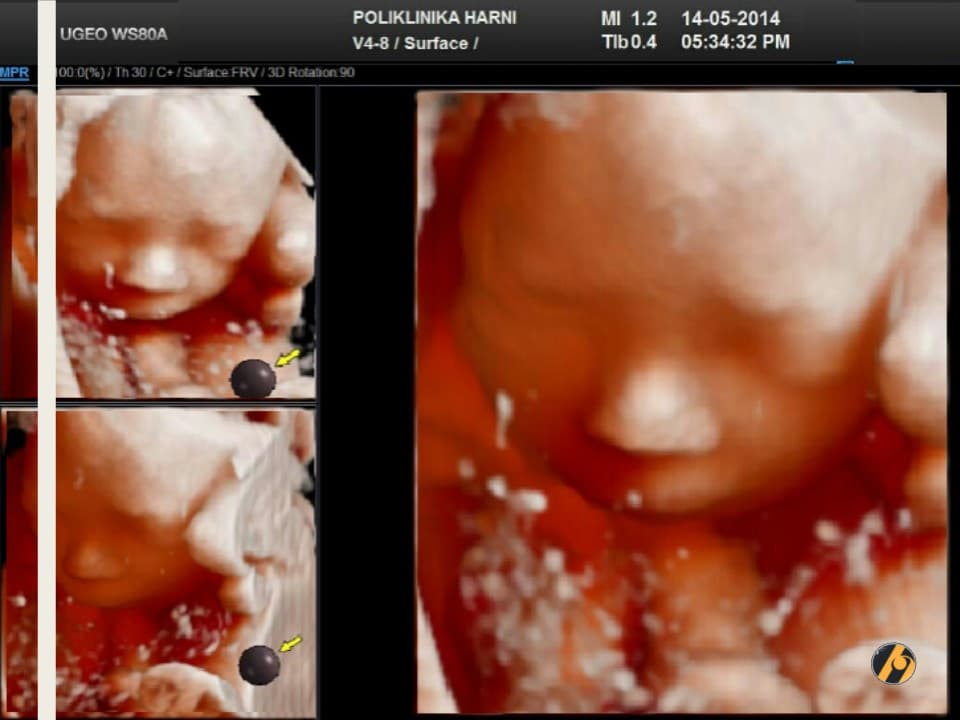

Oko 20. tjedna trudnoće obično se obavlja detaljan ultrazvučni pregled drugog tromjesečja, poznat kao morfološki ultrazvuk ili anomaly scan. Tijekom tog pregleda procjenjuju se razvoj i anatomija fetusa, razvoj mozga, srca i drugih organa, količina plodove vode te položaj i izgled posteljice.

Ovaj pregled omogućuje liječniku da procijeni razvija li se beba uredno te pruža važan uvid u tijek trudnoće, kao i da preporuči dodatne pretrage kao što su fetalna neurosonografija ili fetalna ehokardiografija.